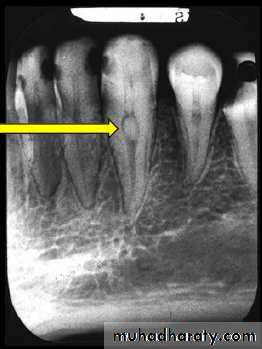

• Clinically:“Pink Tooth” appearance• Radiographic changes:

– Radiolucent enlargement of pulp canal

– Original root canal outline distorted

– Bone changes are seen only when root perforation into periodontal ligament takes place.